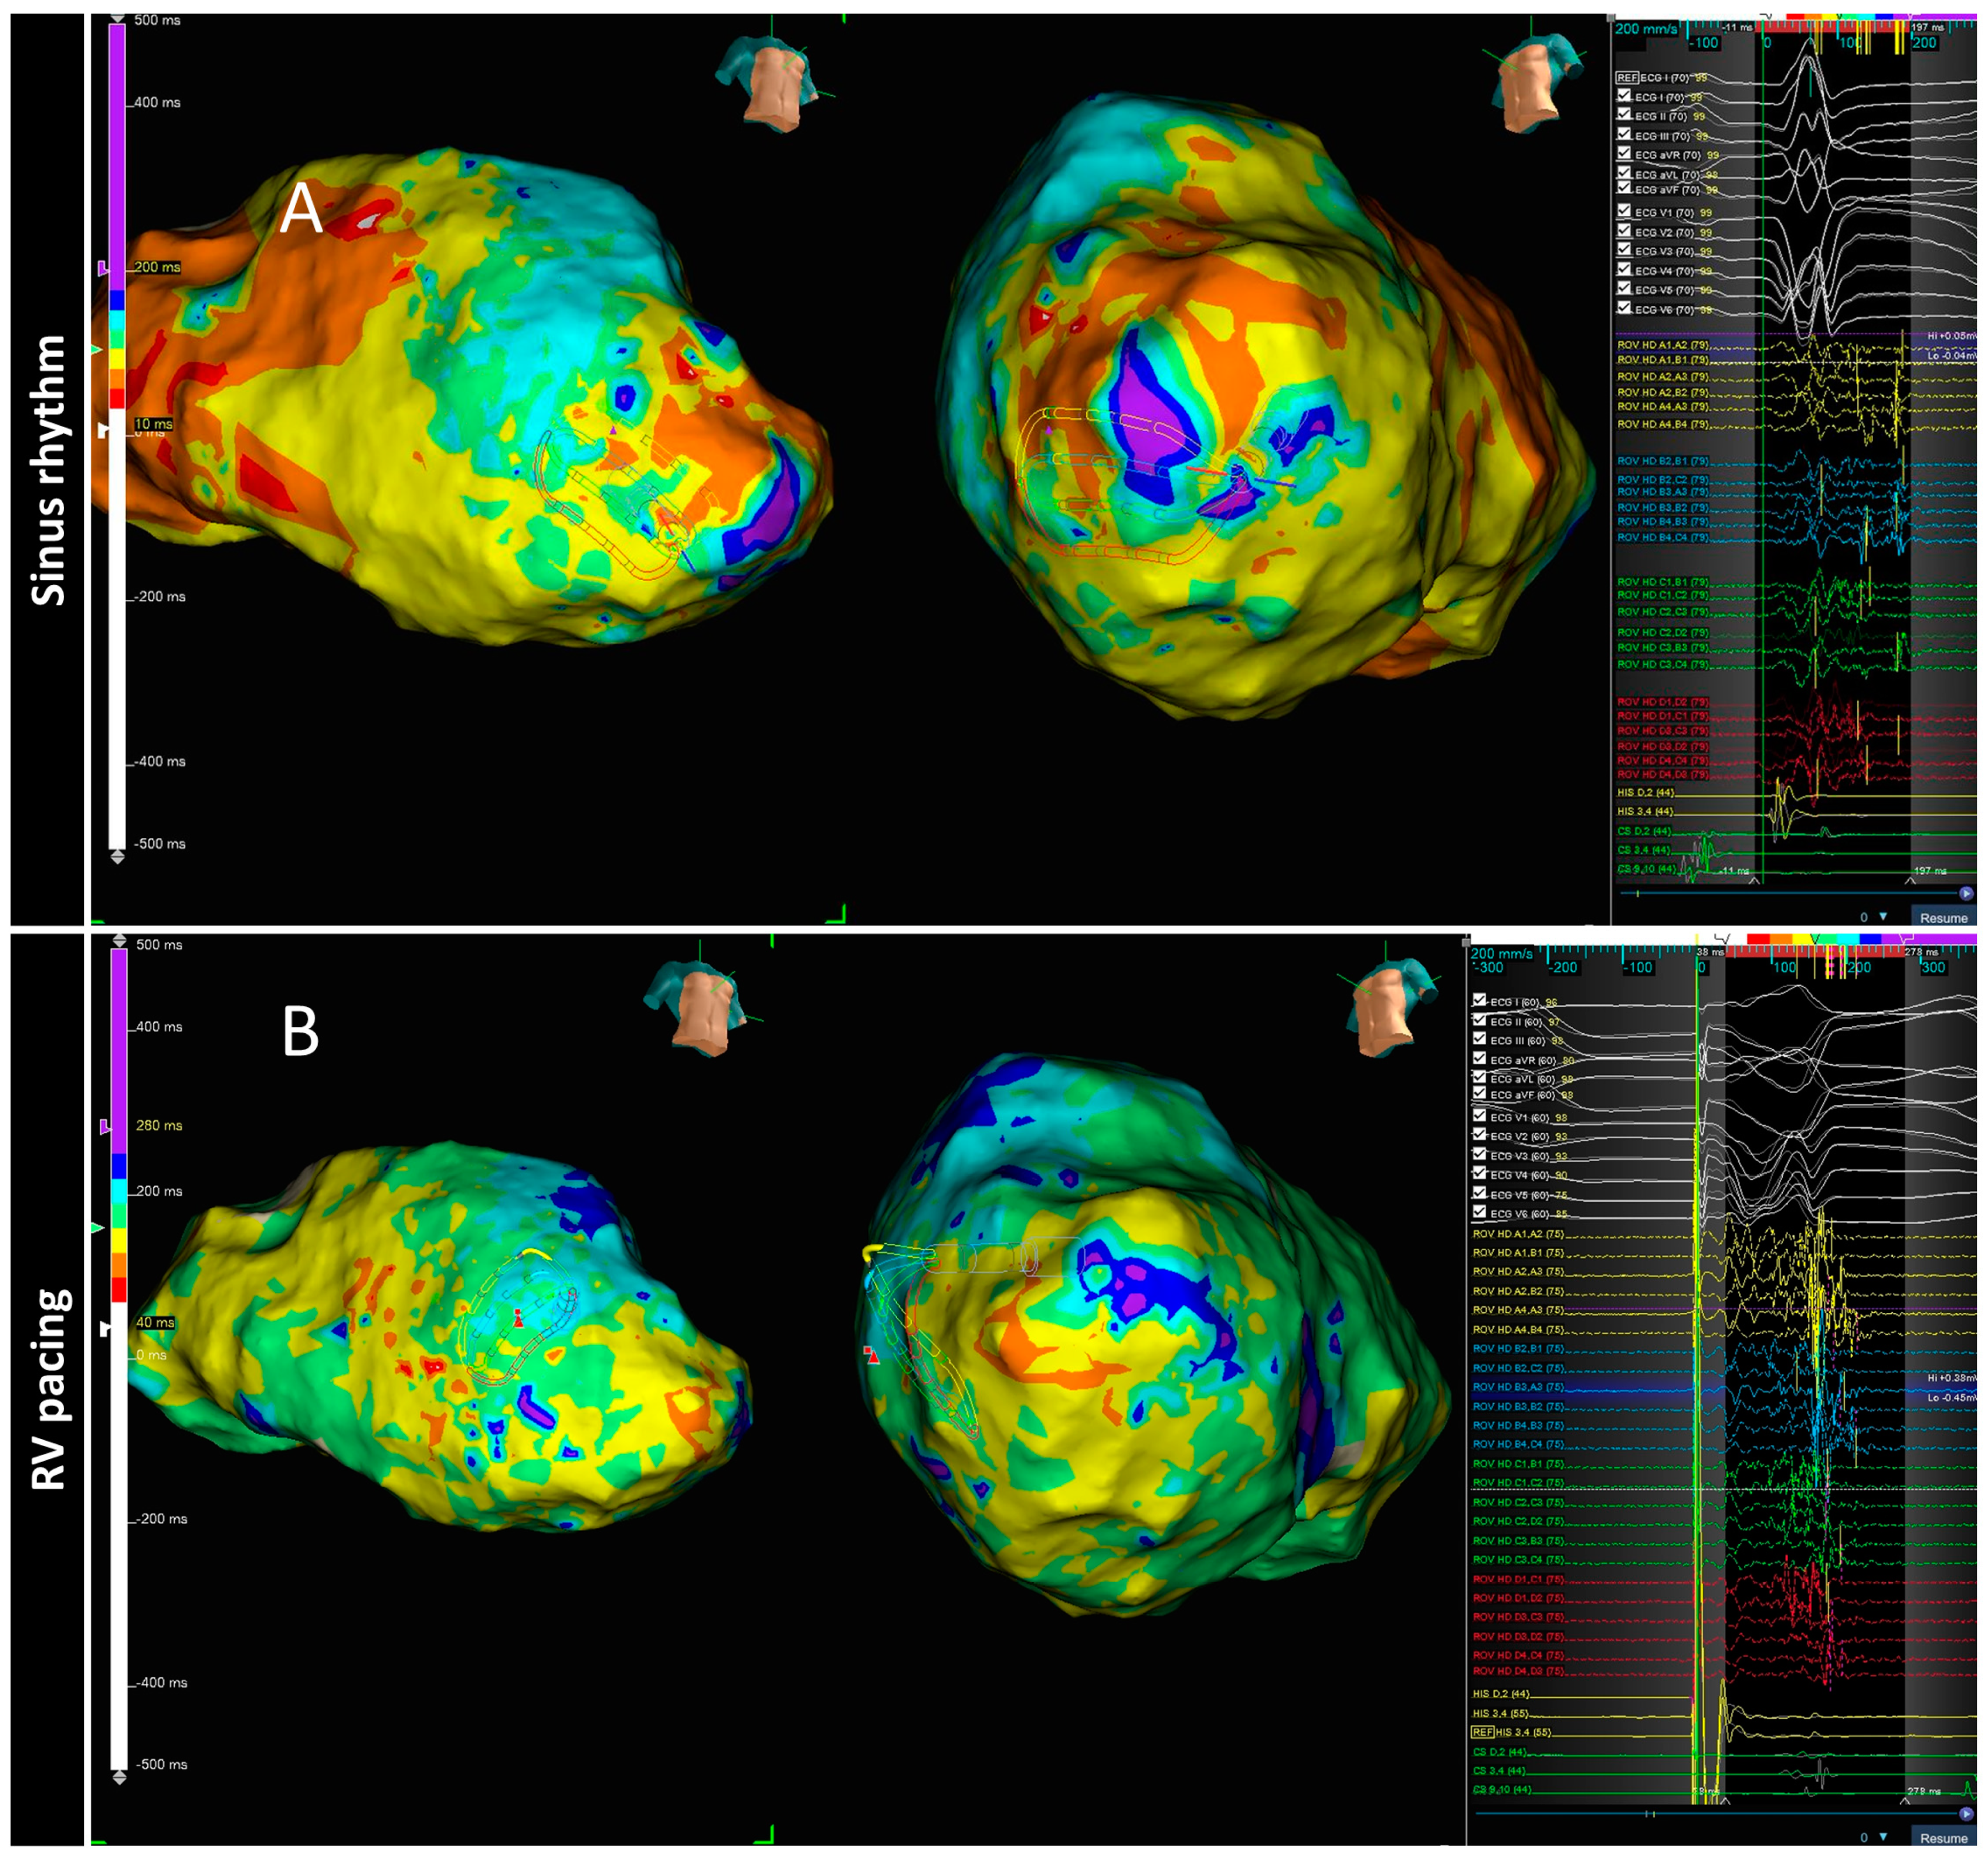

3.6. PHYSIO-VT

- Anter, E.; Neuzil, P.; Reddy, V.Y.; Petru, J.; Park, K.M.; Sroubek, J.; Leshem, E.; Zimetbaum, P.J.; Buxton, A.E.; Kleber, A.G.; et al. Ablation of Reentry-Vulnerable Zones Determined by Left Ventricular Activation from Multiple Directions: A Novel Approach for Ventricular Tachycardia Ablation: A Multicenter Study (PHYSIO-VT). Circ. Arrhythmia Electrophysiol. Lippincott Williams Wilkins 2020, 13, 539–550. [Google Scholar] [CrossRef]